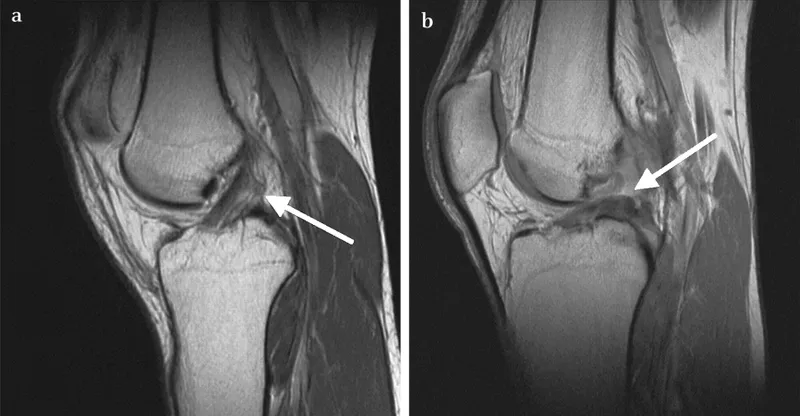

- MRI: ↑ T2 signal, discontinuity, abnormal anterior tibial translation, abnormal ACL slope (sagittal).

- Associated: "Kissing" bone bruises (lateral femoral condyle, posterior tibial plateau), Segond fracture.

⭐ A Segond fracture, an avulsion fracture of the lateral tibial condyle at the site of attachment of the lateral capsular ligament, is pathognomonic for an ACL tear.

- Medial Collateral Ligament (MCL): Valgus stress. MRI: Thickening, periligamentous edema, tear. Pellegrini-Stieda disease (chronic).